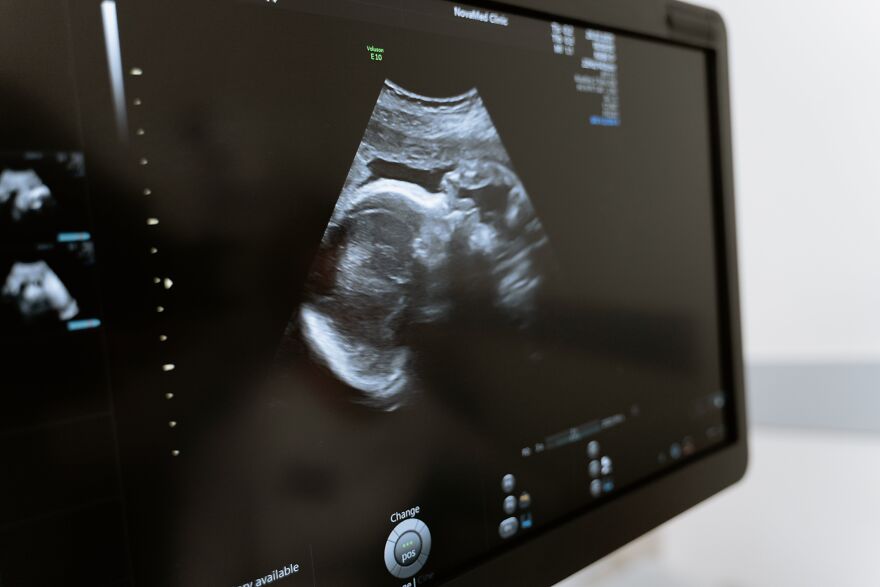

Most people are familiar with ultrasounds. They’re a common medical procedure where a doctor can see inside a patient without hurting them. The best-known examples are prenatal ultrasound appointments during pregnancy, where a doctor checks in on the health of an expected child.

In the case of medical imaging, a doctor moves the transducer around an area of the body. This applies the sound waves to a targeted area, and by moving a little bit, it creates sound wave contrasts that the imaging computer uses for measurements.

As a result, you get an image that can see things inside the patient’s body — whether you’re imaging a developing baby or a kidney stone.